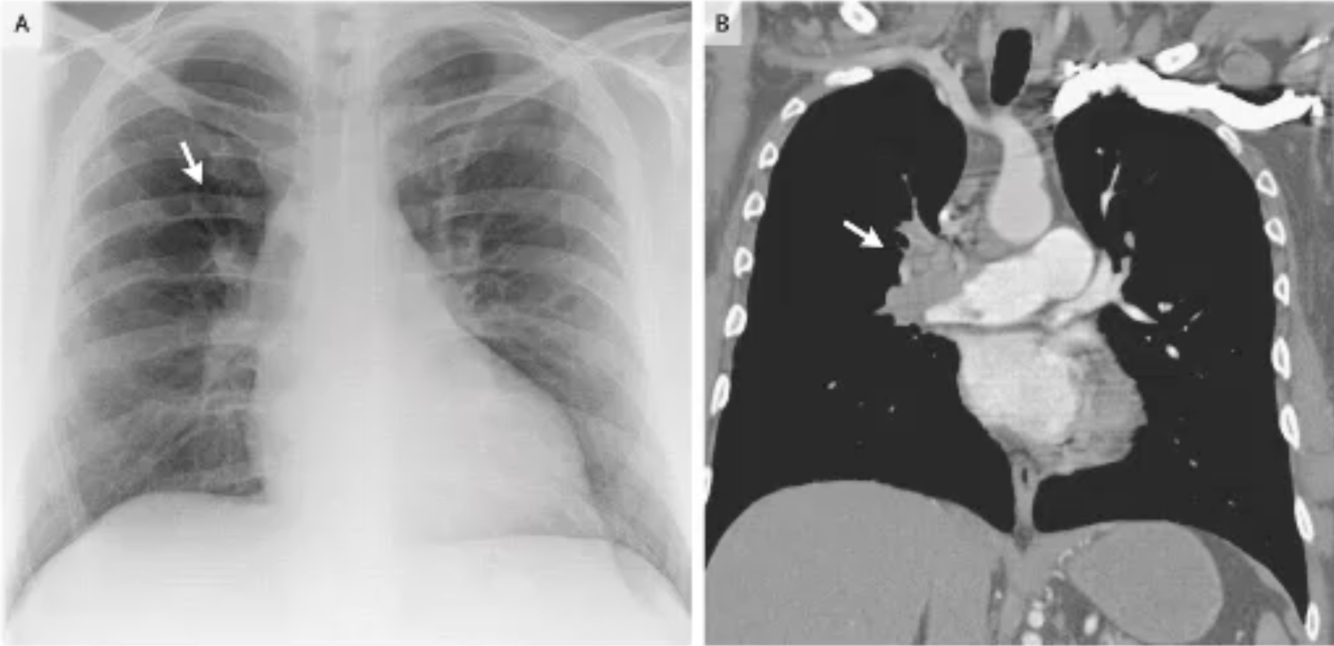

What do these scans show?

Contrast enhanced scans show the location of a pulmonary embolism.

Oligaemia where vessels have collapsed distal to the clot.